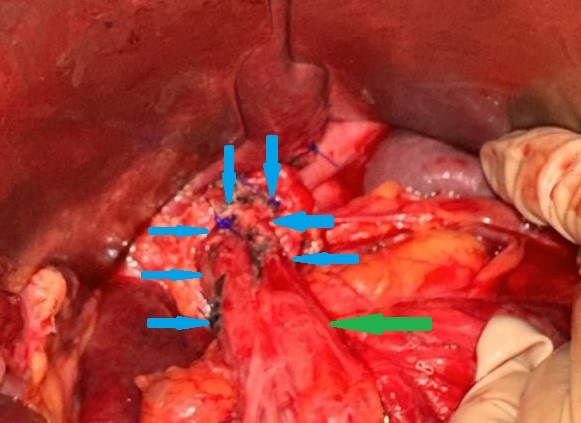

Yellow arrow — Thick-walled gallbladder with gallstones. Blue arrow — Stomach segment. Light blue arrows — Cholecystogastric fistula (Courtesy Dr. V. Penopoulos)